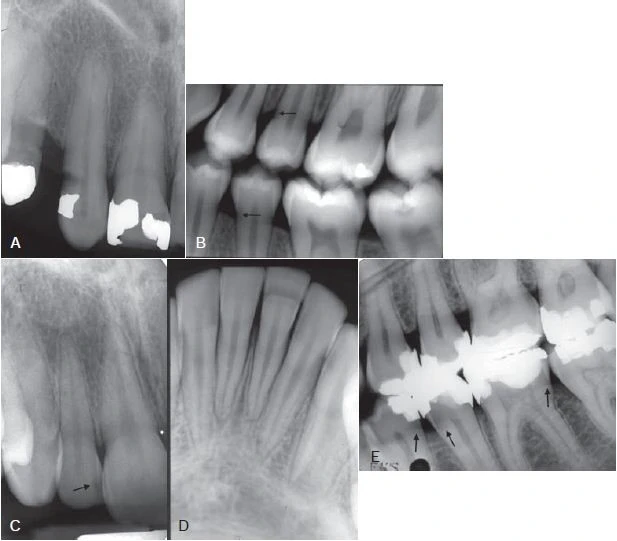

Hình 2. Hình ảnh X quang của tổn thương sâu răng không hoạt động (vùng đen), một nửa xuyên qua men răng vẫn còn nguyên vẹn, với bề mặt được khoáng hoá (mũi tên)

Hình 6. Phim cánh cánh thể hiện sâu răng mặt bên (mũi tên)

Hình 10. Những hình ảnh dương tính giả (mũi tên)

Hình 12. A. Hình ảnh mặt xa răng nanh không nhìn rõ. B. Thay đổi góc chụp cho thấy sâu răng phía xa răng nanh.